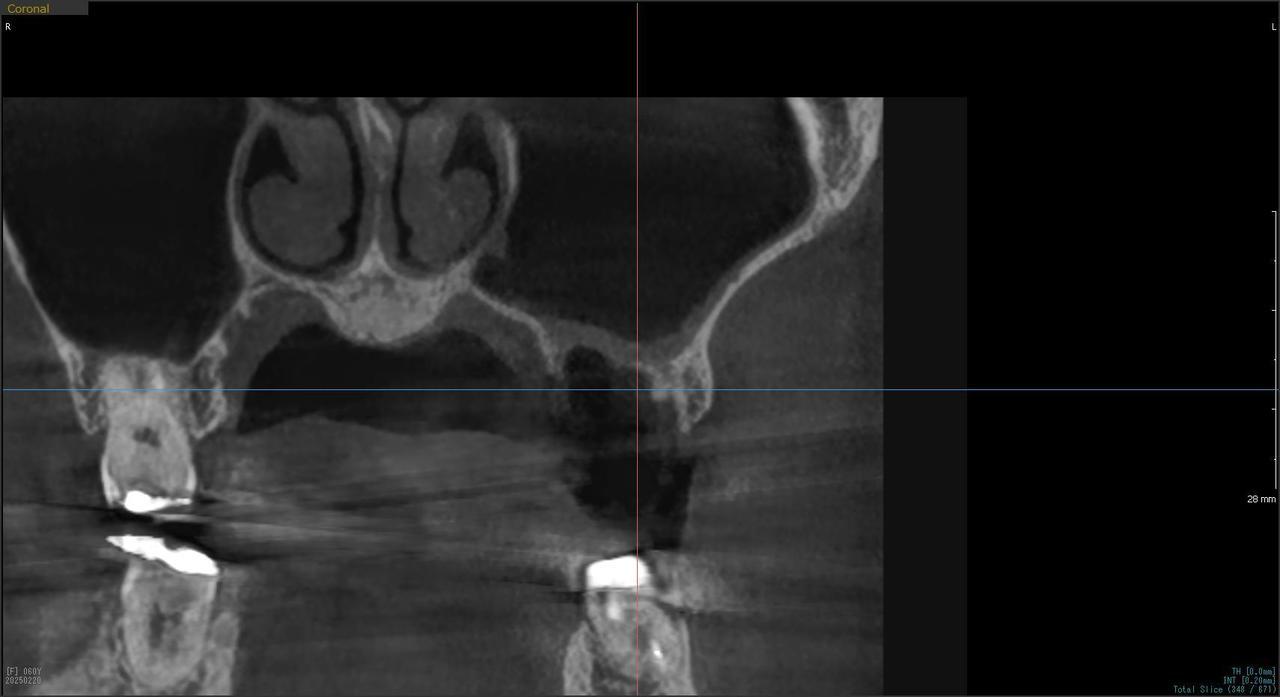

5.右上6番の歯根が破折したに大きな骨欠損を生じたケースに対して、通常なら、大幅な増骨手術(GBRとサイナスリフト)が必要で、最低1年は、かかるケースを、骨補填材なしで、インプラント埋入後、2.5か月で治療を終えたケース

Before

枚方市のインプラントの症例

H・M様 女性 60代

症状としては、左上6番の歯根が歯根が破折したために、炎症が起き、上顎洞底までの及ぶ大きな骨欠損がおきていた、

治療法としては、動揺がひどくなってきて、炎症の症状もあったため、抜歯を希望。抜歯後にインプラント治療を希望したために、CTを撮影したところ、かなりの骨欠損が生じていた。インプラントは不可能か大幅な増骨手術が必要なるようなケースであったが、ご自分の骨が少し残っていた部分にエクストラワイドインプラントで固定をとることと、グラフトレスサイナスリフトを併用する計画を立て、インプラント埋入術を施行。2か月後、インプラントがデータ測定上安定したために、光学印象で印象を行い、2か月半後に上部としてジルコニアクラウンを装着して治療を終えています。

治療結果として、大幅な骨欠損があったが、2か月半という短時間で治療を終えることができた。通常のサイナスリフト等の大幅な増骨手術を行った場合、患者様に、肉体的、金銭的、時間的な負担をかけることになったが、グラフトレスサイナスリフトとエクストラワイドインプラントを使用することにより、そのことを避けることができた。

治療の期間・回数:治療回数インプラント埋入後6回

治療の価格:363000円(税込)

治療費の内訳:インプラント基本料(フィックスチャー(メガジェンインプラントANYONE) 及び手術費用、投薬費用、レントゲン費用、インプラント上部費用(アバットメントおよびジルコニアクラウンの費用用)330000円(税込み)左上6グラフトレスサイナスリフト費用 33000円(税込)

治療のリスクや副作用:手術後に、痛みや腫れ、出血、合併症などを引き起こす可能性があります。噛む感覚がご自身の歯と異なる場合があります。見た目がご自身の歯と異なる場合があります。手術後にメインテナンスを継続しないと、インプラントが抜け落ちる可能性があります。